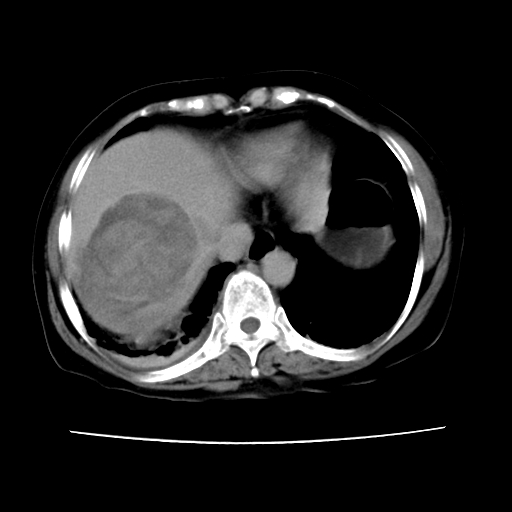

2008-6-10ct平扫

ct增强

6月份ct片显示肝内巨大混杂密度团块,伴包膜下积液(内含液液平面),增强多无明显强化。只能考虑肝占位病变,并肝内、血膜下血肿。肝ca并出血多见,而肝血管瘤并破裂出血少见。

从平扫+增强及治疗后复查片,病变明显缩小,不考虑肝癌出血可能,还是考虑为良性病变可能性大;单纯血肿并包膜下积液吧,病变强化没法解释,肝血管破裂出血吧,增强不符合典型血管瘤的表现,良性肿瘤破裂出血吧,复查片看来好像也不太支持(没做强化也不太好说)。本人还是考虑单纯肝内血肿并包膜下积液,强化是不是血管有外渗。